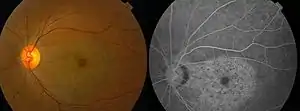

Chloroquine retinopathy

| Chloroquine retinopathy [2] | |

With continued drug exposure, there is progressive development of a bilateral atrophic bull's-eye maculopathy and paracentral scotomata, which may in severe cases ultimately spread over the entire fundus, causing widespread retinal atrophy and visual loss.

Profound abnormalities detected with visual field and multifocal electroretinography testing can be observed in the presence of a normal retinal appearance. Retinal examinations are advised for documentation, but visible bull's-eye maculopathy is a late change,[6] and the goal of screening is to recognize toxicity at an earlier stage. Annual screening should begin after 5 years (or sooner if there are unusual risk factors).[5]